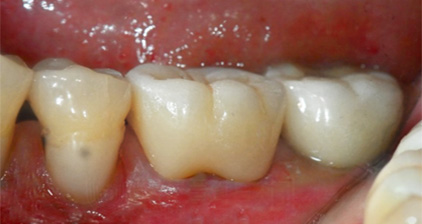

하루크라운 치료 전

하루크라운 치료 후

치료 시작과 동시에 치아를 삭제하고

컴퓨터 촬영을 통해 정확한 정보를 얻습니다.

하루플란트치과 원내 기공소에서

즉시 보철물을 제작하여

임시 치아 과정 없이 1~2시간 이내에

최종 보철물을 장착합니다.